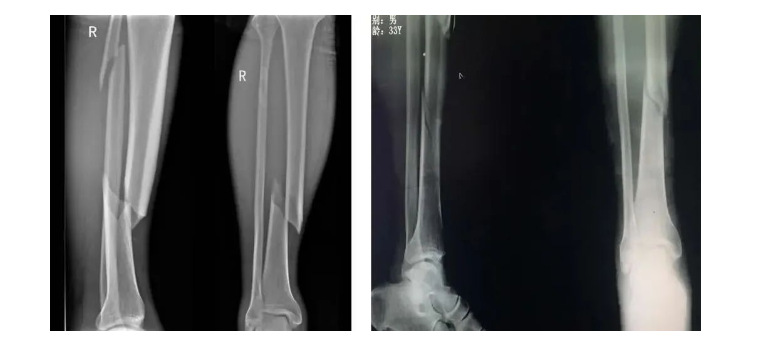

脛骨干是常見的骨折好發(fā)類型之一,占全身骨折的13.7%。脛骨下端具有血運(yùn)代償性不佳、軟組織覆蓋少等解剖特點(diǎn),一旦出現(xiàn)骨折,軟組織受損,局部血供不佳,將會(huì)增加骨折愈合的難度,加之合并腓骨骨折概率高、穩(wěn)定性不佳,選擇適宜的手術(shù)方案十分必要。

脛骨干中上段橫截面呈三角形,下1/3處橫截面呈四方形。中下1/3交界處比較細(xì),又是形態(tài)發(fā)生改變的部位,為骨折好發(fā)部位。

脛骨的前1/3僅有皮膚覆蓋沒有肌肉覆蓋,骨折時(shí)骨斷端易戳破皮膚形成開放性骨折,即使是閉合性骨折大多數(shù)脛骨骨折都合并皮膚和皮下組織損傷。脛骨中段缺少肌肉覆蓋,且脛腓骨周圍有四個(gè)筋膜室。骨筋膜室綜合征發(fā)生率高于其他骨折。